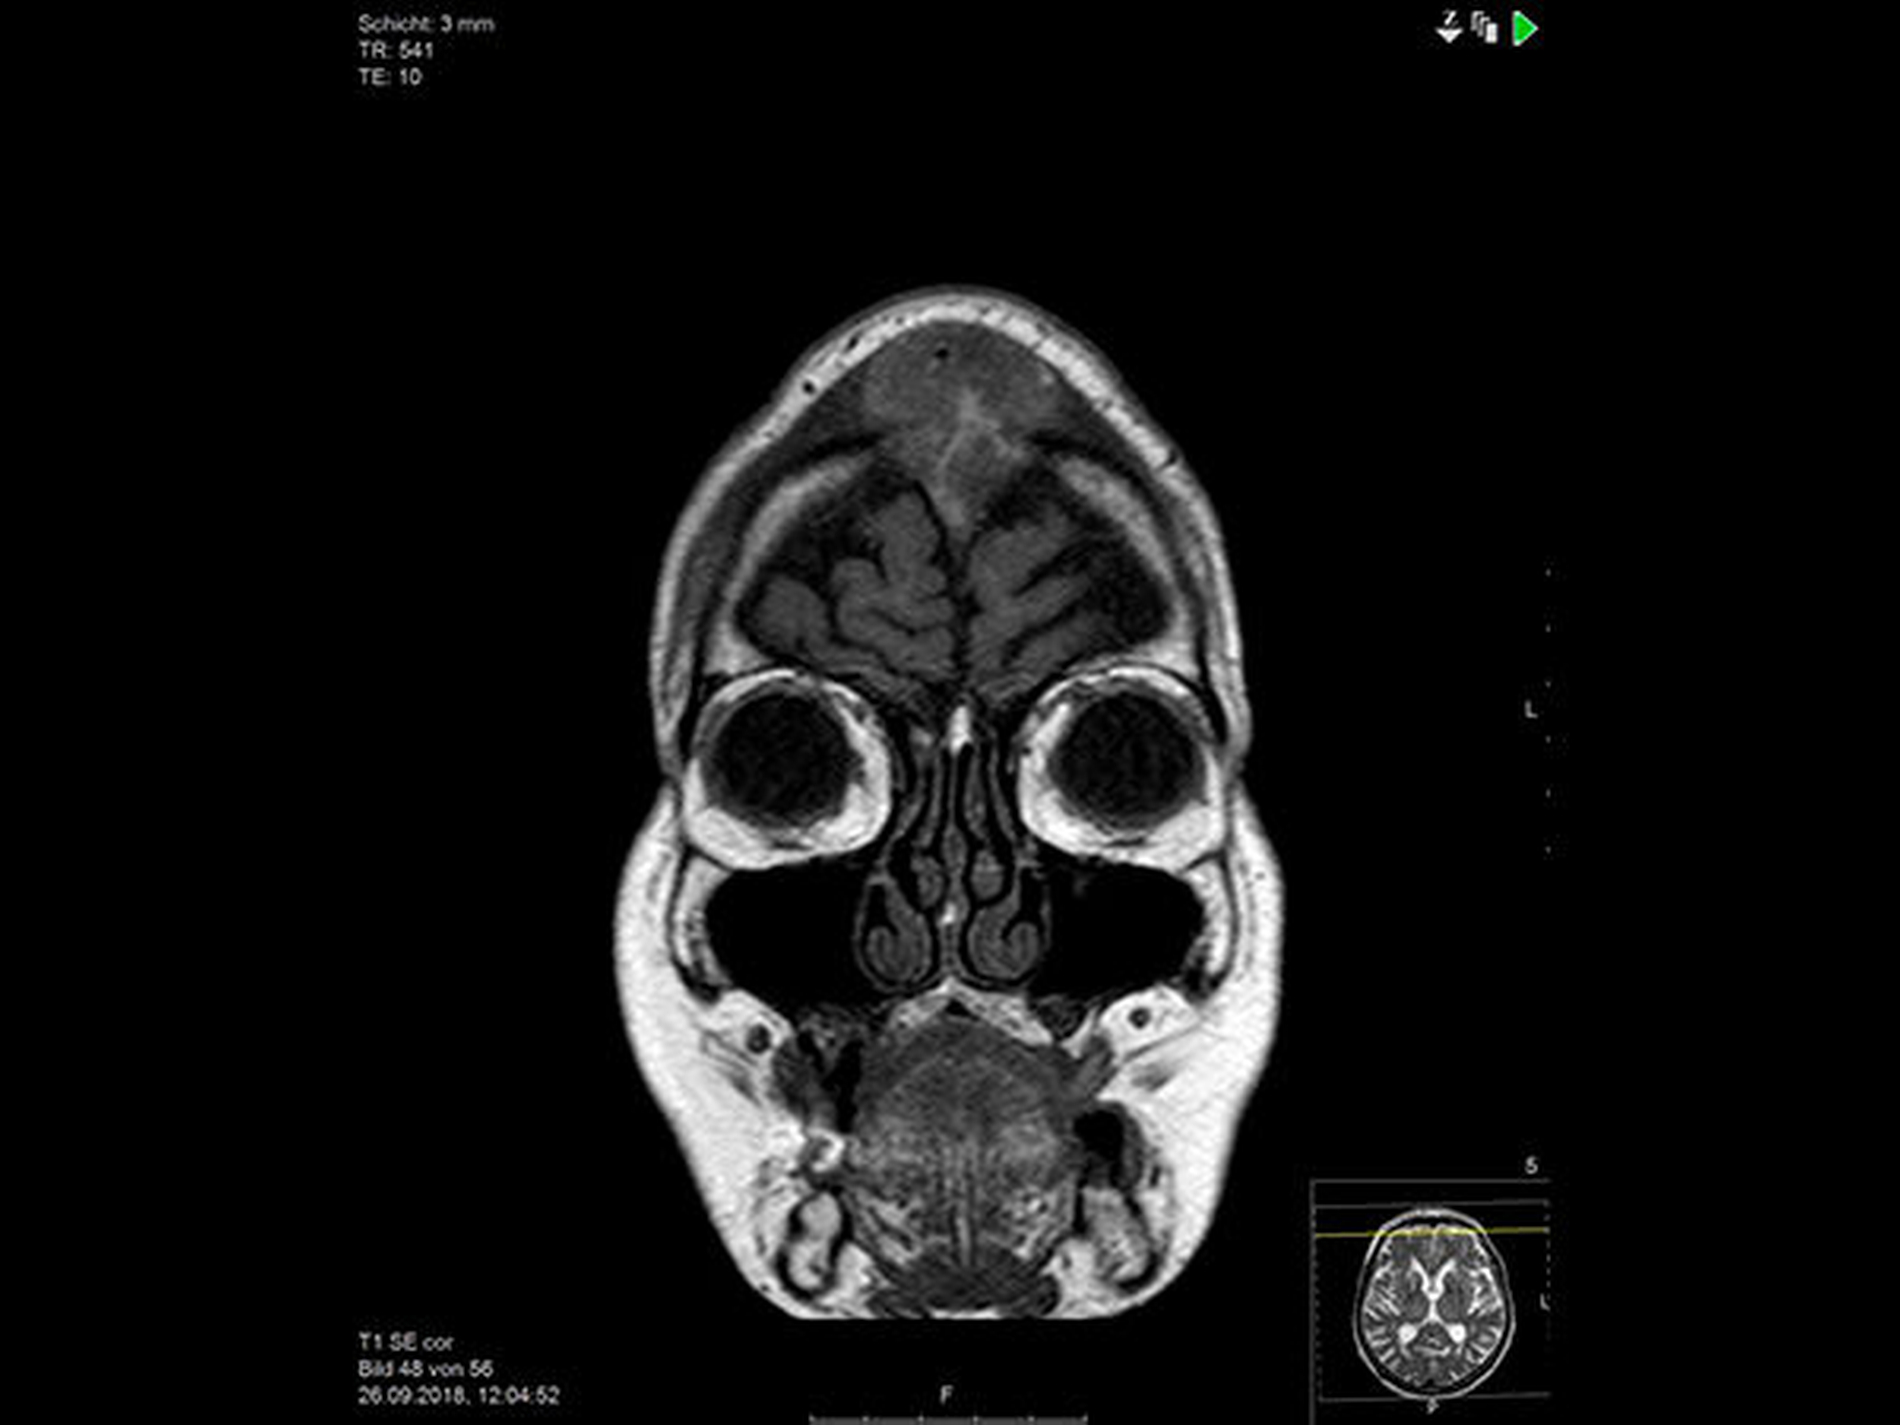

Im nun durchgeführten bildgebenden Staging wird im kranialem MRT die Infiltration des Sinus sagittalis superior bestätigt, eine weitere intrakranielle Filiarisierung ausgeschlossen (Abbildung 3).